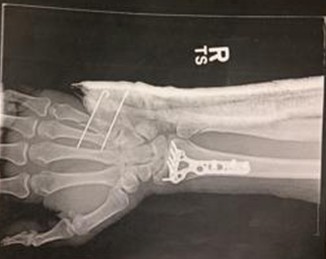

When Mark was operating his bicycle against traffic, one sunny afternoon, a motorist failed to see him, crossed over the white fog line and struck him. Mark was thrown from his bicycle and suffered devastating injuries including a fractured leg and a fractured arm and wrist which required surgery and hardware to put him back together.